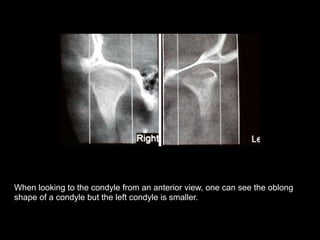

When looking to the condyle from an anterior view, one can see the oblong

shape of a condyle but the left condyle is smaller.